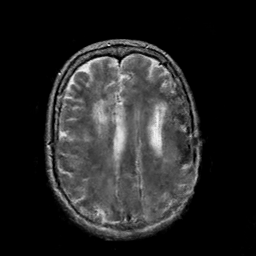

In this paper, we propose a bidirectional learning model, known as dual contrast cycleGAN (DC-cycleGAN), for medical image synthesis from unpaired data. Specifically, a dual contrast (DC) loss is formulated that leverages the advantage of samples from the source domain as negative samples to indirectly build constraints between real source and synthetic images via discriminators, and synthesize images more related to the target domain by enforcing the synthetic images to fall far away from the source domain. In addition, structural similarity index (SSIM) [35] and cross-entropy (CE) [48] are integrated into the DC-cycleGAN structure to avoid disappearing gradient information that is caused by a mean absolute error (MAE) and synthesizing irrelevant images. SSIM considers luminance [35] and CE converges fast as its back-propagation error is less than MSE [28]. As can be seen in Figs. 1 and 2, using SSIM and CE with dual contrast can generate more clear and accurate MR images as compared with that of MAE and MSE, and SSIM and CE without dual contrast loss. Although both SSIM and CE with dual contrast and without dual contrast generate similar CT images, SSIM and CE with dual contrast quantitatively generate better images as shown in Table 4. The experimental results indicate that DC-cycleGAN is able to consider more complex features such as structure in synthesizing images and produce remarkable results as compared with other state-of-the-art methods reported in the literature.

Tables 3 and 4 show the results of MR and CT synthesis, respectively. As can be seen, all components play vital role in both tables. SSIM & CE (w) performs significantly better than other losses in synthesizing MR images. This also can be seen visually in Fig. 1. In contrast, SSIM&CE (w) performs slightly better than SSIM&CE (wo) in synthesizing CT images, both generate more or less similar CT images (see Table 4).